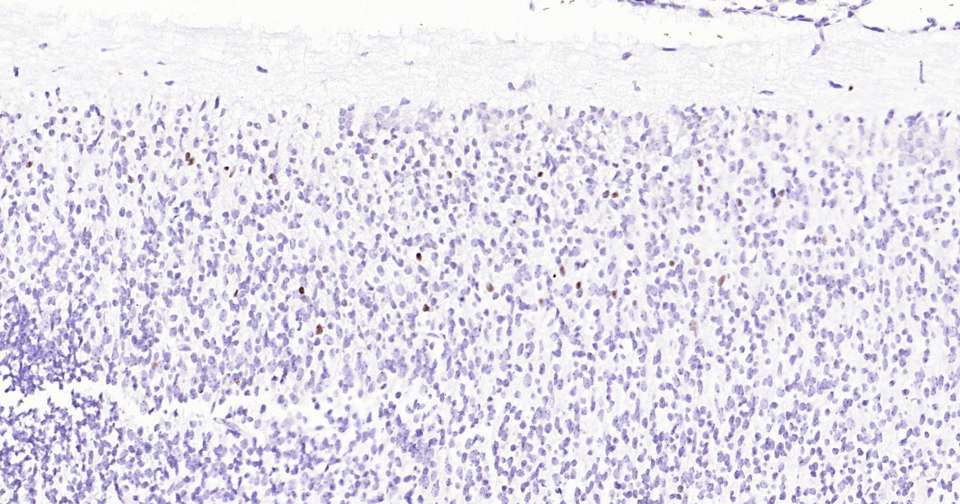

Immunohistochemical analysis of paraffin embedded mouse embryo tissue slide using IHC0358M (Mouse WT1 Kit).